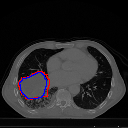

Moreover, we performed a qualitative analysis on the results produced from the two cases. We observed two things that happen in the absence of wavelet transforms -

-

1.

The predicted tumors seem to have frequent outliers

-

2.

In most cases, the predicted tumor seems to be enlarged and the edges of the tumors are not properly detected

These observations have been demonstrated in Figure 7.

Figure 7 shows the occurrence of outliers in the absence of wavelet transforms and an inability to accurately determine tumor edges in this case. The intuition concerning the former observation is that without wavelet transforms, texture information is relatively lost and the model perceives similarly shaped structures to be tumors as well. The second observation is also related to the fact that wavelet transforms can capture the texture better. In absence of it, the model cannot predict or justifiably limit the extent of the area that the tumor boundary should encompass. This results in inflated tumor areas and inaccurate tumor sizes.